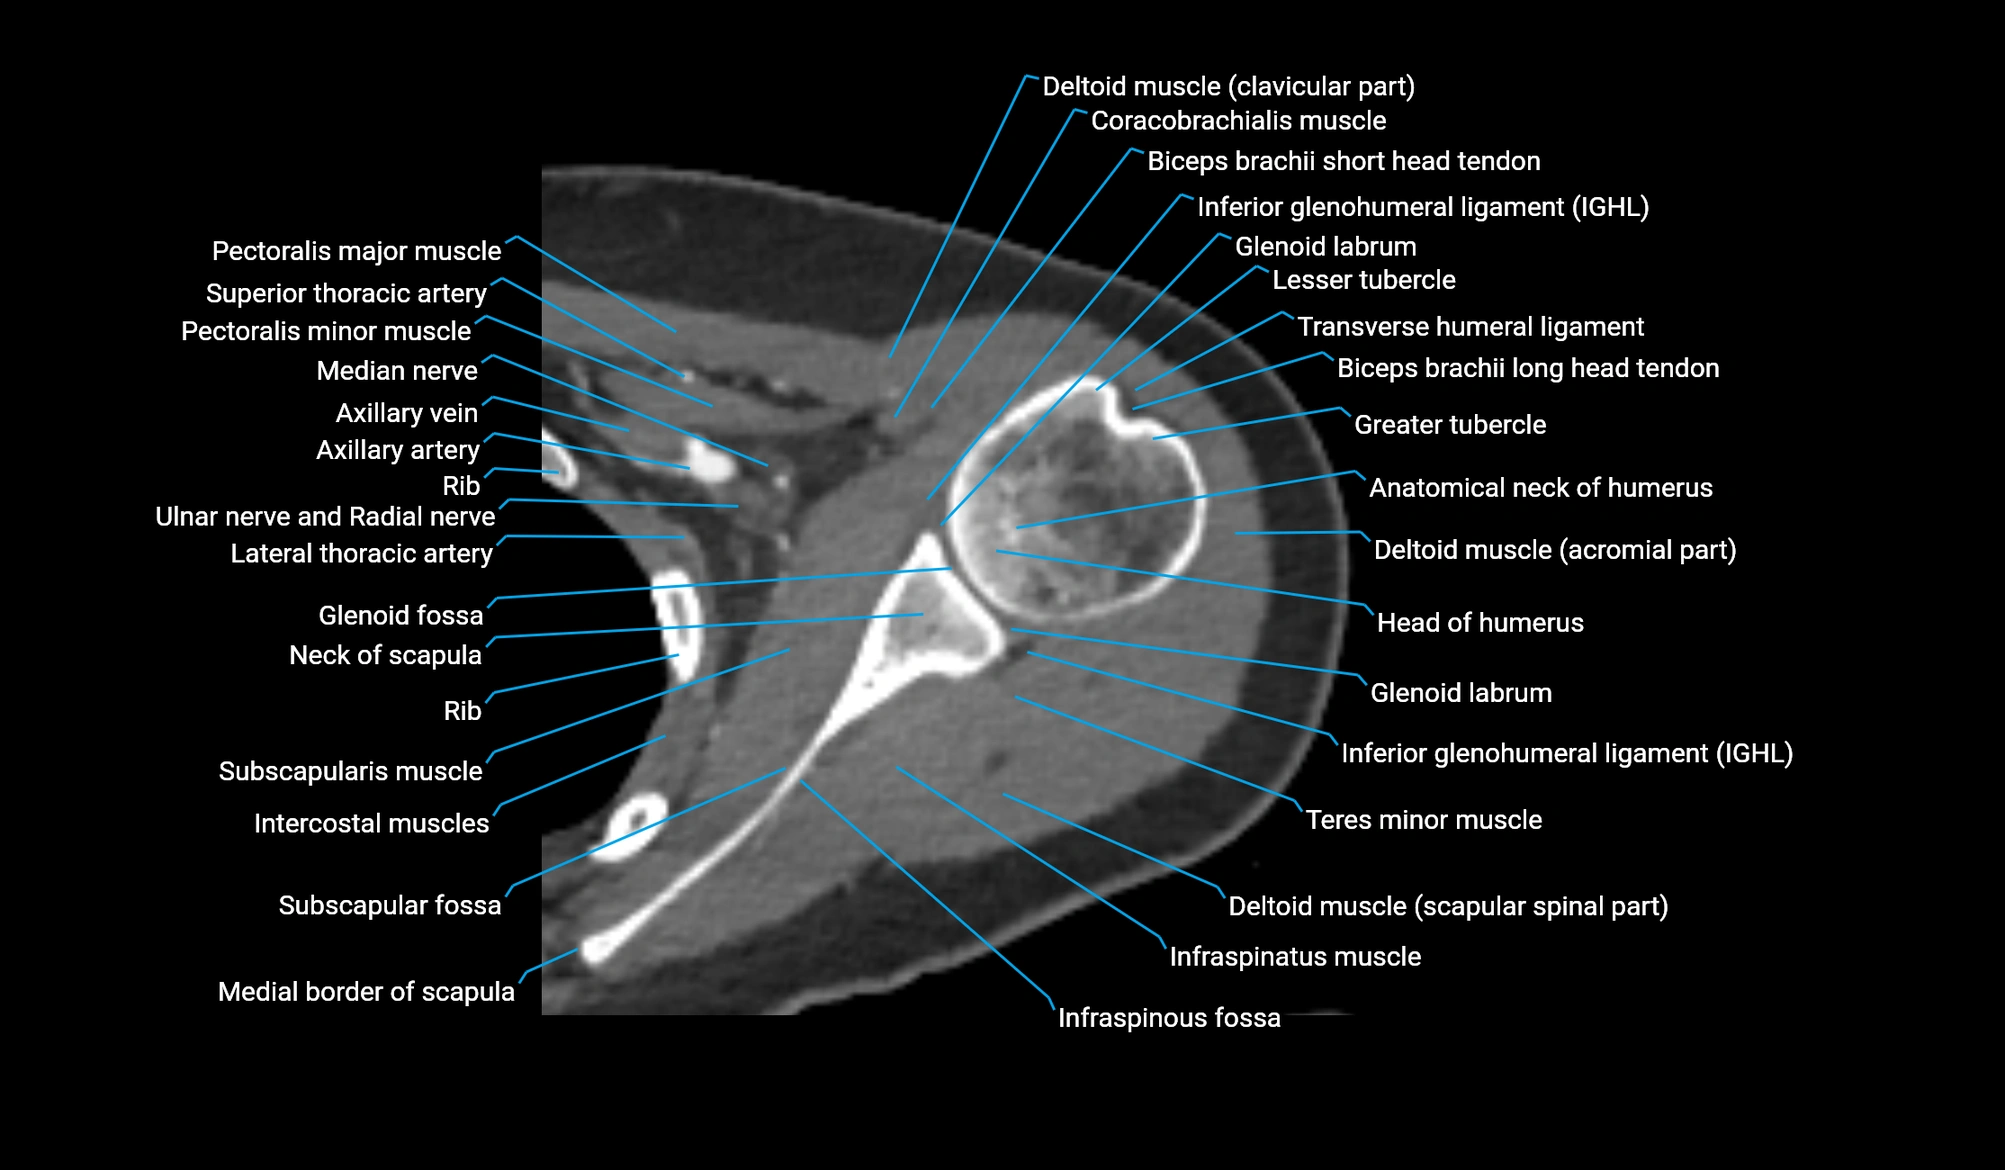

- Head of humerus

- Anatomical neck of humerus

- Greater tubercle of humerus

- Lesser tubercle of humerus

- Glenoid labrum

- Inferior glenohumeral ligament

- Glenoid fossa

- Neck of scapula

- Subscapularis muscle

- Infraspinatus muscle

- Teres minor muscle

- Coracobrachialis muscle

- Clavicular part of deltoid muscle

- Scapular spinal part of deltoid muscle

- Lateral border of scapula

- Medial border of scapula

- Subscapular fossa

- Pectoralis major muscle

- Pectoralis minor muscle

- Axillary lymph nodes